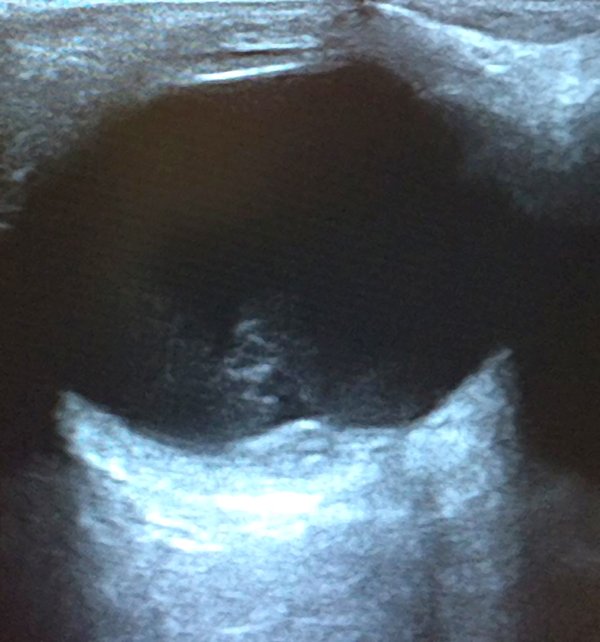

En la exploración se encontró una agudeza visual en OD de visión de cuenta dedos a 1 metro y en ojo izquierdo (OI) de 10 décimas. A la biomicroscopía no se detectaron particularidades en ambos ojos, sin presencia de reacción en cámara anterior. La presión intraocular era de 11 mmHg en AO. La paciente no pudo realizar el test de Amsler en su OD y en el OI era normal. Fondo de ojos: en el OD se observó una lesión macular con resto de retina aplicada sin hemovítreo ni lesión vascular periférica. El OI estaba normal. Se solicitó interconsulta a centro de mayor complejidad donde le realizaron una tomografía de coherencia óptica (OCT), una ecografía ocular modo B, que trajo la paciente a las 48 horas. En el OCT se observó la extensa afectación macular (fig. 1) también reflejada en la ecografía (fig. 2), interpretándose el cuadro de hemorragia prerretinal en área macular en contexto de maniobra de Valsalva. Se evaluó posibilidad quirúrgica con retinólogo, que viajó a examinar a la paciente a Río Grande, pero considerando riesgos/beneficios y en el contexto traumático de su reciente aborto, la paciente decidió no tratarse quirúrgicamente y mantuvo tratamiento tópico quedando con colirio de bromfenac 0,09% cada 6 horas durante 4 meses.

Figura 1. Secuencia de imágenes tomadas mediante tomografía de coherencia óptica donde se observa la desorganización estructural de la mácula.

Figura 2. Ecografía modo B. Se observa la afectación macular en la zona inferior de la imagen correspondiente al área de la hemorragia prerretinal.